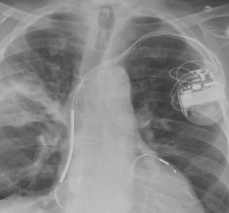

Andrew L. Chan, MD, MB, FCCP, FRCP; Jordan D. Fein, MD; Timothy E. Albertson, MD, PhD, FRCP

<p>THE CASE: An 81-year-old retired obstetrician who had never smoked tobacco presented with a 6-week history of cough with clear sputum, fever, chills, and a 30-lb weight loss. He...